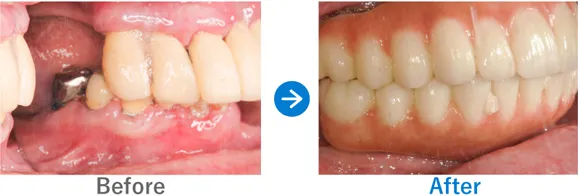

Case4

フルマウスインプラントで、食事も旅行も楽器も楽しめる人生の再スタート!

入れ歯を使用中。重度の歯周病で残っている歯もぐらぐらしている

上顎 オールオン4ダブルザイゴマ、下顎 オールオン4

10,318,000円(上顎6,743,000円、下顎3,750,000円/内訳:上顎オールオン4(ノーベルザイゴマインプラント4本)、下顎オールオン4(ストローマンインプラント4本)、3Dモデルガイド*、仮歯、セデーション、ボツリヌストキシン注射、3D模型、保証10年)

来院の背景

入れ歯を作ったものの、重度の歯周病で前歯もぐらぐらしており噛むことが難しく、入れ歯をかけている歯もダメージを受けている状態でした。入れ歯をやめて、友人と気兼ねなく食事をしたり、旅行を楽しんだり、楽器を吹いたりすることをご希望です。

治療結果

ご家族のうち、歯が悪いのは患者さまのみでコンプレックスがあったそうです。今回、思い切って治療を受けてよかった! とおっしゃっていました。30代から糖尿病の治療薬を服用されています。糖尿病は歯周病のリスクが高いので、今後もインプラント周囲炎のリスク管理が重要です。